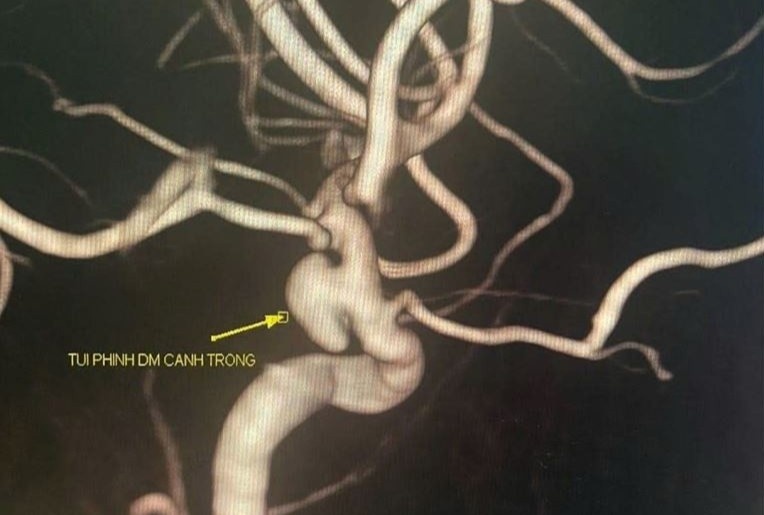

Đau đầu, run tay thoáng qua, cô gái trẻ phát hiện “quả bom nổ chậm” trong não

Chỉ với những triệu chứng thoáng qua như đau đầu, run tay, một nữ bệnh nhân 33 tuổi ở Quảng Ninh bất ngờ phát hiện túi phình mạch não nguy hiểm trong lần khám sức khỏe tổng quát. Ca can thiệp kịp thời đã giúp chị thoát khỏi nguy cơ đột quỵ và tử vong.